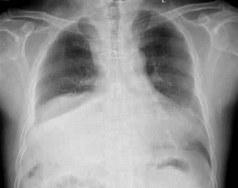

縱膈里的組織器官多,因而可發生多種多樣的腫瘤,即使腫瘤很小也會引起循環、呼吸、消化和神經系統的功能障礙。兒童縱膈腫瘤的發病率較成人為低,但癌變機會多。約有2/3的病兒早期有咳嗽、低熱、呼吸困難等症狀,這是和兒童胸腔容量小有關。有些病兒在胸部X線檢查時偶爾發現,如果是惡性腫瘤則有貧血和消瘦現象。發現上述症狀應及早就醫,醫生可由胸部X攝片來確定腫瘤部位和大小,通過超音波檢查得知腫瘤的性質

(1)X線檢查:常規胸部正側位,X線照片及透視檢查,可作出初步診斷。進一步檢查方法有:支氣管造影,斷層造影,血管造影及縱隔充氣造影等。

3、X線檢查可見縱膈腫塊陰影或囊性陰影。